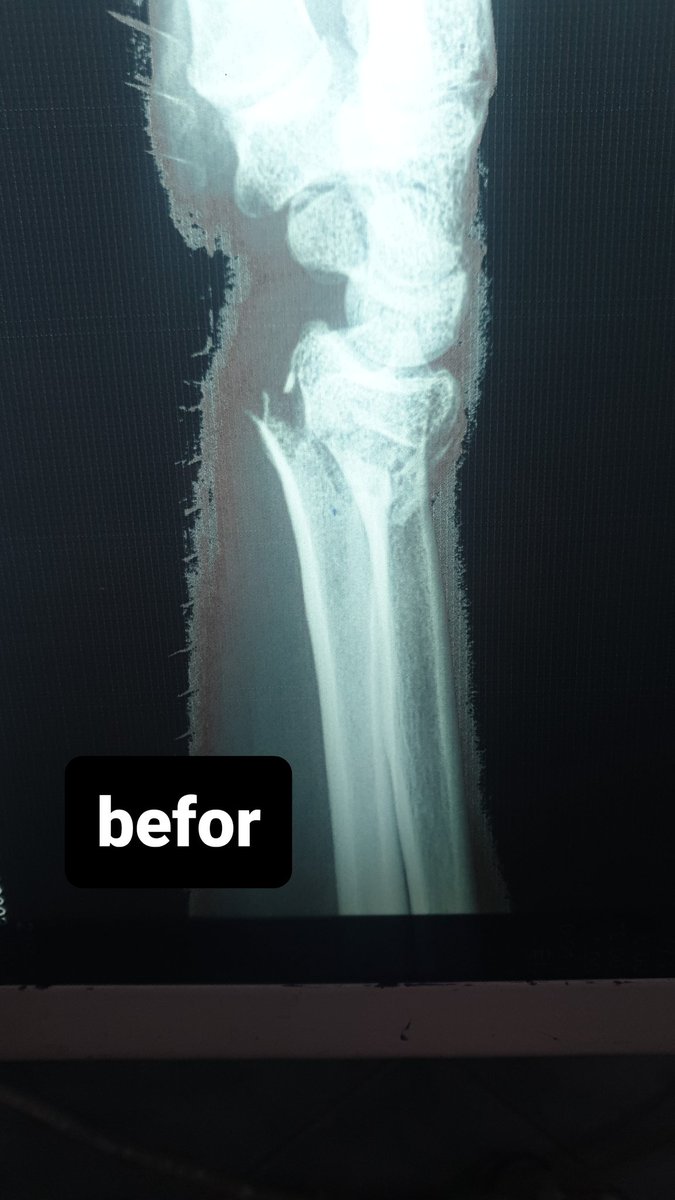

58 male fall from height last week !

Hx: HTN , CAD

Medicine :Aspirin 81 , Clopidogrel

When I aspirate hematoma there was about 6 ml blood

this is the pre_after reduction and the follow up today

He is not elderly in shape and body he looks like 40 !

1/2